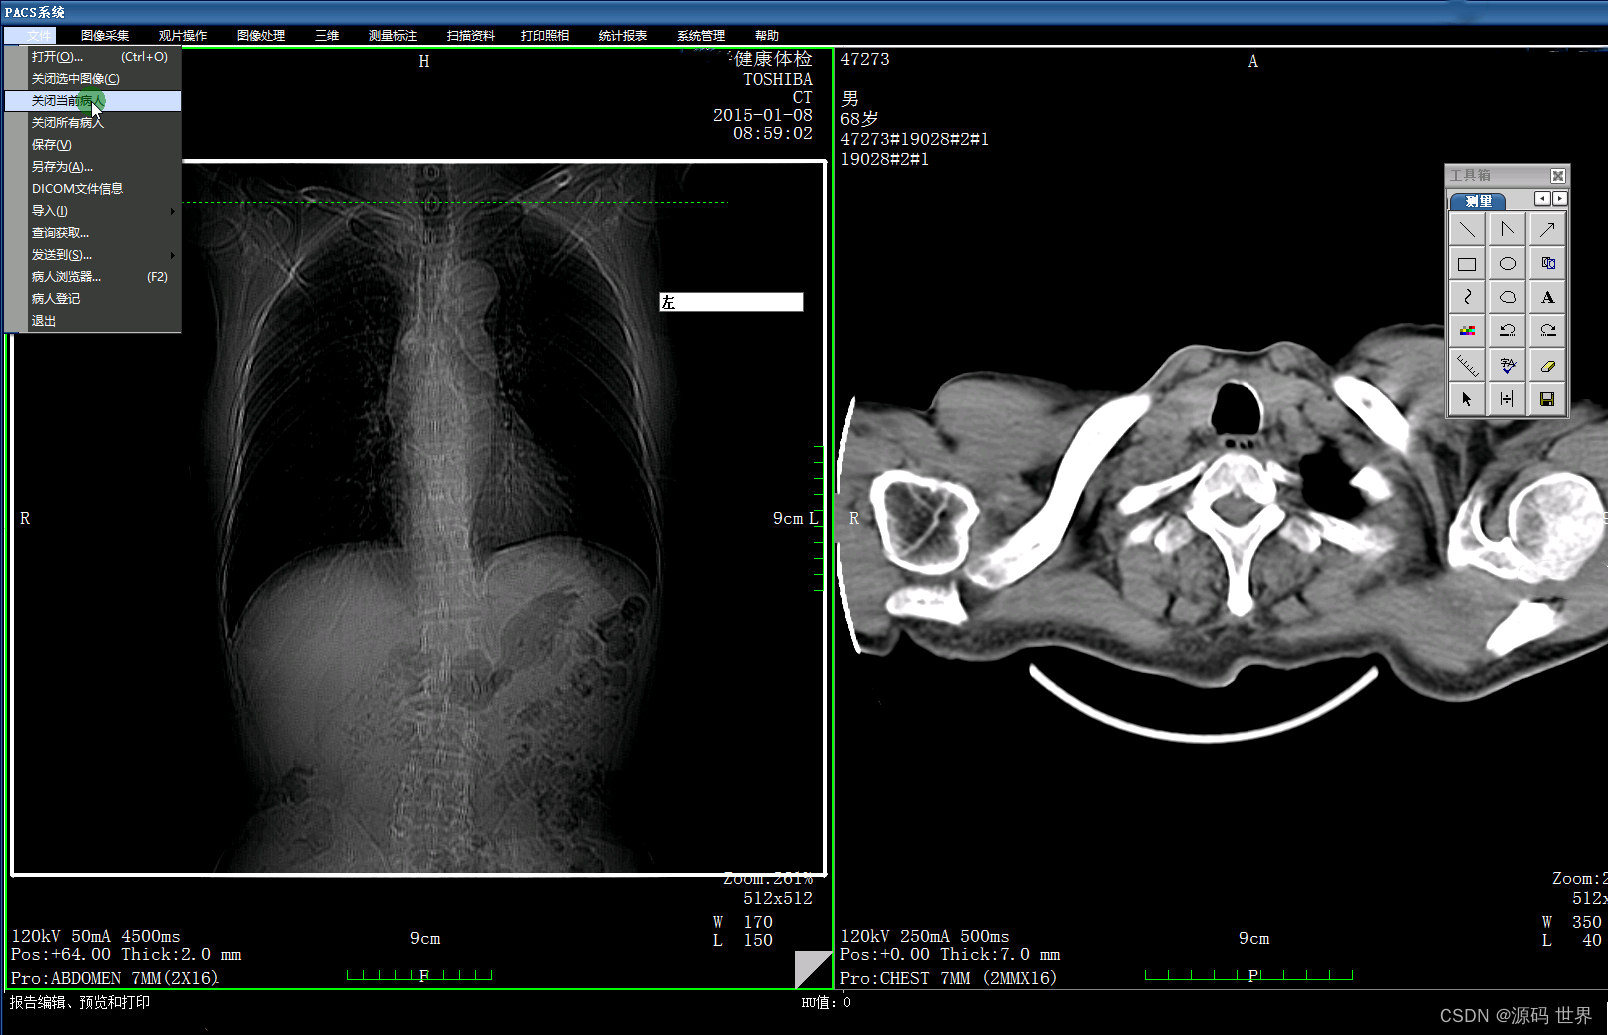

PACS系统的作用

影像归档与通信系统(PACS)则专注于影像资料的存储、检索、分发和通信。PACS系统可以联接不同的影像设备(如CT、MR、XRAY、超声、核医学等),存储和管理图像,以及图像的调用与后处理。PACS系统也可以与其他系统如HIS、RIS集成,以提高工作效率和检查准确性。